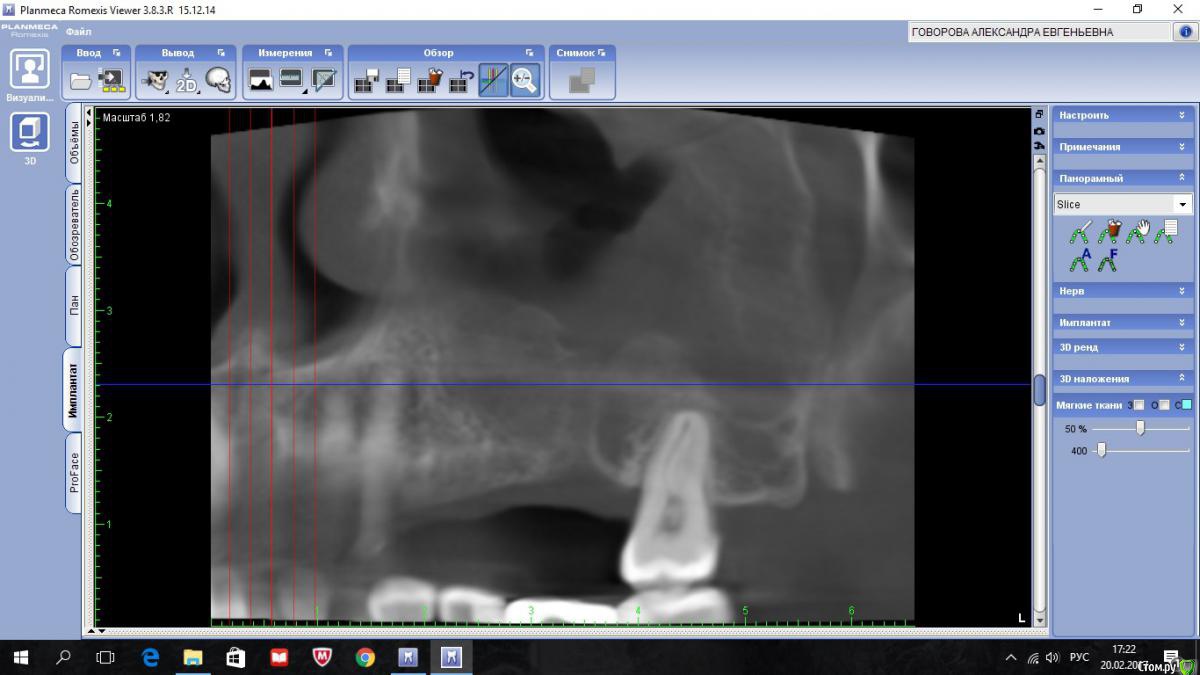

kriokov Опубликовано 20 февраля, 2017 Поделиться Опубликовано 20 февраля, 2017 пациентка 56 лет Радикальная гайморотомия в чло в сентябре 16.Удален 16. клкт до экзекуции клкт спустя месяц клкт примерно через полгода 2 Ссылка на комментарий

kriokov Опубликовано 20 февраля, 2017 Автор Поделиться Опубликовано 20 февраля, 2017 А разве Колдуэлл-Люк тут сильно виноват?не знаю, смотря что кто видит на снимках. Изначально--клиники синусита не было, смотрел пациентку на предмет иплантации во 2 сегменте, увидел рентгенологически тень с куполом в пазухе слева, 26 был живой на тот момент, отправил к лорикам, лорики в чло, кафедральные посмотрели- отпунктировали, вроде как получили кистозное наше содержимое. Соперировали.Посмотрел ее через месяц после гайморотомии. Нос дышал, чувствительность выпала, парус во рту по своду, но не критично. Решил подождать 6 мес.И вот сейчас картина -- клиники гайморита нет, дышит. Чувствительности нет, не восстановилась. По своду понятно- все как было. А вот рентгенологически картинка интересная-- там где не закрывалось латеральное окно, мягкие ткани туда и ввалились (наверное что на подобие рубцовых тканей), киста судя по всему была, как раз почти по верхней границе купола идет рост новообразованной кости. Кость по высоте 10-12 мм в обл 24 , 25, 26. Кто виноват (Колдуэлл или Пушкин) мне по барабану, я не эксперт, и не кафедральный. Думаю, если бы была возможность латеральное окно сеткой или мембраной перекрыть, пролапса мягких тканей внутрь не было бы. Ну и из разряда экзотики-- можно и на одном столе отработать члх и лорику. ИМХО 2 Ссылка на комментарий

kriokov Опубликовано 22 февраля, 2017 Автор Поделиться Опубликовано 22 февраля, 2017 вопрос основной как работать дальше с пациенткой. 1. носовое дыхание свободное2. естественное соустье работает, дырка в нижнем носовом тоже не заросла3. лор посмотрел -- дал заключение, что это не та патология, которую ЛОРики пользуют4. болты вкрутить- не вопрос, как понимаетеЧего делать с дырой?Варианты -- 1. соперировать, -- убрать мягкие ткани аккуратно из пазухи, поставить или фольгу или сетку-- окно то закрою конечно, заоодно гляну чего с подглазничным, на кт отверстия не видать , или снесено, или просто не визуализируется. НО , но, но- останется имеющаяся контрапертура в нижний носовой. Через год , полтора, может появиться симптоматика , как у пациентов после радикальной2. не трогать ничего, поставить болты.Буду говорить с пациенткой Ссылка на комментарий